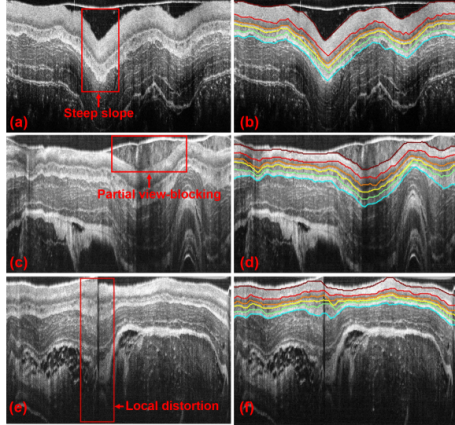

研究通过应用基于L1-L0的图像去噪与平滑高分辨率成像处理技术、图论及最短路径搜索优化技术等进行活体组织层析图像的自动分割与分析,突破微米级活体组织结构的分析和信息提取。并在此基础上,开展了活体组织的光学着色研究,模拟显微成像原理对组织分层着色,凸显组织内部细胞元及结构,实现组织的定量分析。

特殊成像条件下的图像分析与组织的分层提取

活体组织分层着色及内窥重建